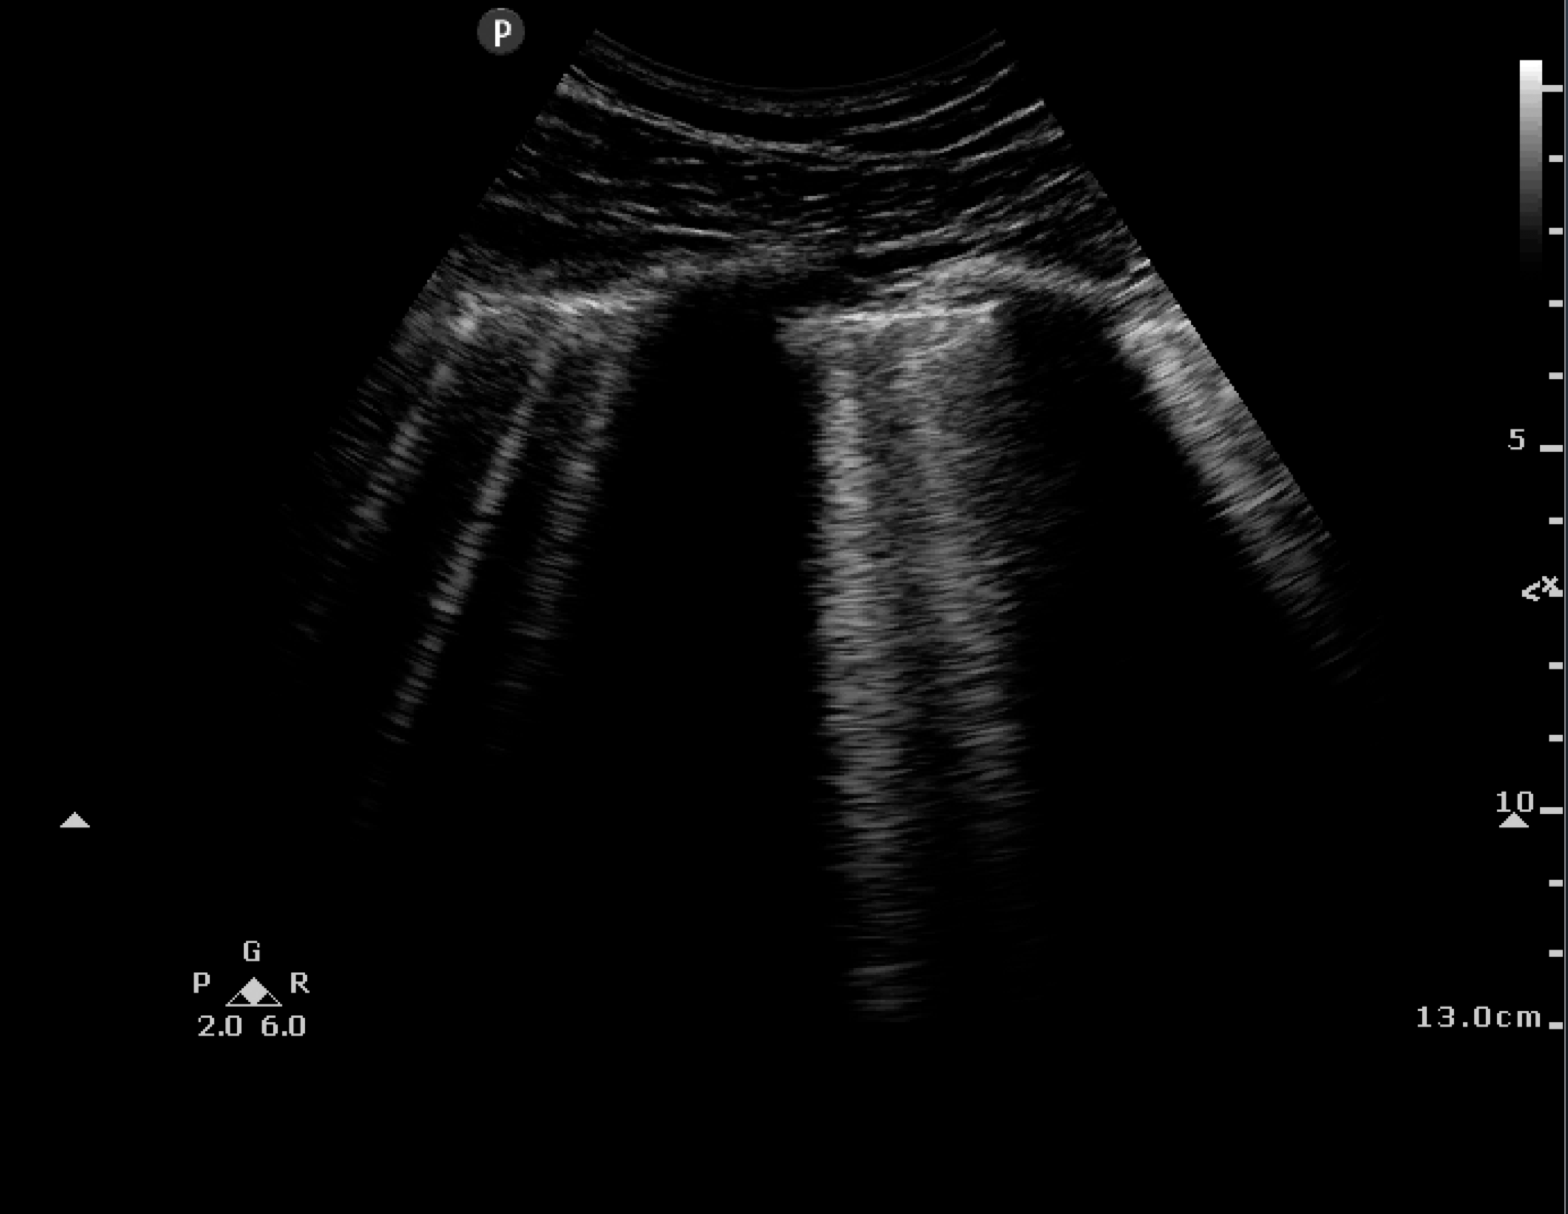

POCUS is now part of the core curriculum for emergency medicine residents. Identifying B-Lines on thoracic ultrasound can be used to identify interstitial fluid.

- Intervention: Bedside ultrasound by EM resident assessing for three or more B-lines using eight-zone thoracic ultrasound on thoracic exam preset and curvilenear transducer. All EM residents received 30-minute lecture on technique and recognition of sonographic B-lines by the ED director of ultrasonography.

Case Resolution: You get out the ultrasound machine and find B-Lines suggestive of acute heart failure. These ultrasound findings are verified by your attending.